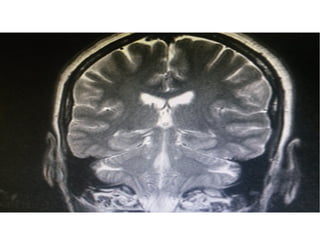

Exames de imagem e liquor

• TC de Crânio: Inespecífica: Atrofia cortical, aumento

de sulcos, lesões vasculares maiores.

• RNM de Crânio: Visualiza bem hipocampos,

substância branca e cinzenta, lesões vasculares

menores, delimita melhor área de atrofia.

• SPECT: Hipofluxo parietal ou parietotemporal

• PET: com PIB, Pittsburgh compound B

• Liquor: Proteína Tau, fosfotau, csf e betaamilóide.

• Novidade: Exame de retina em betaamilóide